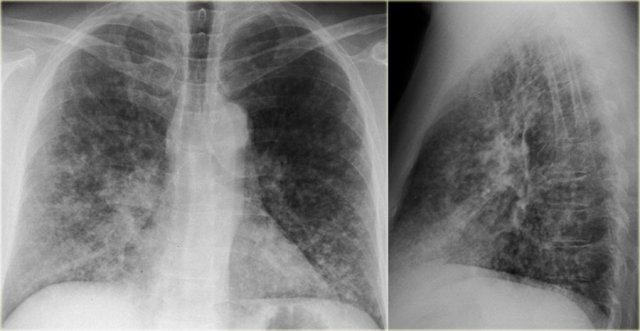

Lao

Lao nguyên phát thường không có biểu hiện lâm sàng.

Ở 5% cá thể bị nhiễm, miễn dịch không đủ và bệnh tiến triển có triệu chứng lâm sàng, được gọi là bệnh nguyên phát tiến triển (9).

Lao hậu nguyên phát là sự tái hoạt của nhiễm trùng tiềm ẩn và xảy ra ở 5% bệnh nhân bị nhiễm.

Trên phim X quang ngực, biểu hiện là đông đặc có tạo hang ở các phân thùy đỉnh của thùy trên và thùy dưới.

Lao kê là kết quả của sự lan tràn theo đường máu.

Đây là hình ảnh bệnh nhân lao hậu nguyên phát với tạo hang ở thùy trên phổi trái.

Bệnh nhân này nhập viện lần đầu với phim X quang ngực bên trái.

Hãy quan sát kỹ các hình ảnh trước.

Sau đó tiếp tục đọc.

Các dấu hiệu bao gồm:

- Các đám mờ bờ không rõ lan tỏa, có thể là các vùng đông đặc nhỏ.

- Hang ở thùy trên phổi phải.

Có thể nhận định đây là tái hoạt của lao tiềm ẩn.

Cấy đờm dương tính với vi khuẩn lao.

Phim X quang ngực chụp vài năm sau (bên phải) cho thấy:

- Xẹp thùy trên phổi phải

- Lệch khí quản

- Xơ hóa và tạo hang ở phần còn lại của thùy trên

- Xơ hóa tối thiểu và tạo hang ở thùy trên phổi trái.

Điều này được đánh giá rõ hơn trên CT.